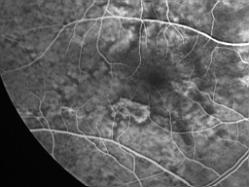

ASSOCIATION STRIES ANGIOIDES ET DYSROPHIE MACULAIRE RETICULEE

NEOVASCULARISATION